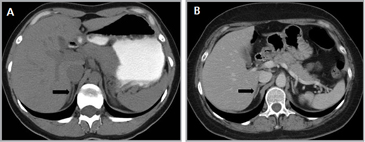

En la TC no contrastada las glándulas suprarrenales normales son homogéneas y simétricas, con una densidad muy similar a la del parénquima renal adyacente (Figura 1 a). Con un medio de contraste ev la glándula suprarrenal se opacifica en forma homogénea, similar al hígado o al bazo (Figura 1 b). Si la cantidad de tejido adiposo retroperitoneal es abundante las glándulas suprarrenales pueden aparecer enteramente rodeadas por grasa y su delimitación es más fácil (Figura 2 a); lo inverso ocurre en pacientes muy delgados con escasa grasa retroperitoneal (Figura 2 b). En RM, en secuencias ponderadas en T1 y T2 convencionales tienen una intensidad de señal homogénea, hipointensa respecto de la grasa adyacente e iso o hipointensa con respecto del parénquima hepático (Figura 3 a y b). En los cortes coronales se aprecia mejor la forma y la posición de las glándulas suprarrenales (Figura 3 c).

Figura 1. Glándula suprarrenal normal en tomografía computada. Cortes axiales de tomografía computada, donde se identifica la morfología normal de la glándula suprarrenal derecha (flecha) en fase no contrastada (a), y tras el uso de medio de contraste endovenoso (b).